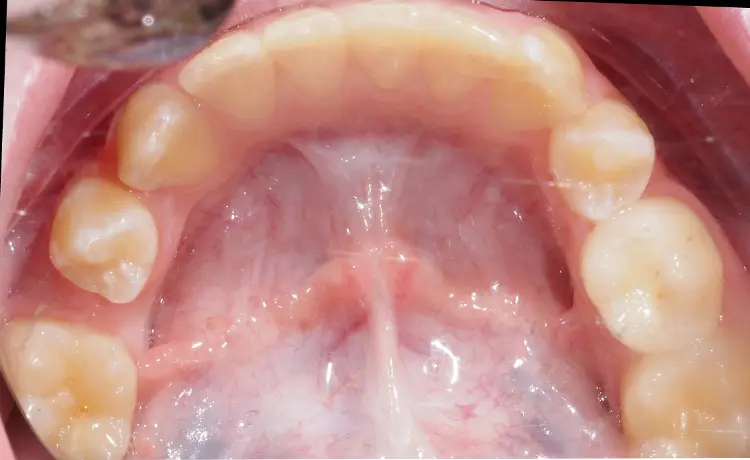

• Częściowych lub pełnych aparatów stałych, które stopniowo przesuwają zęby i odtwarzają właściwą przestrzeń.

efekt leczenia ortodontycznego